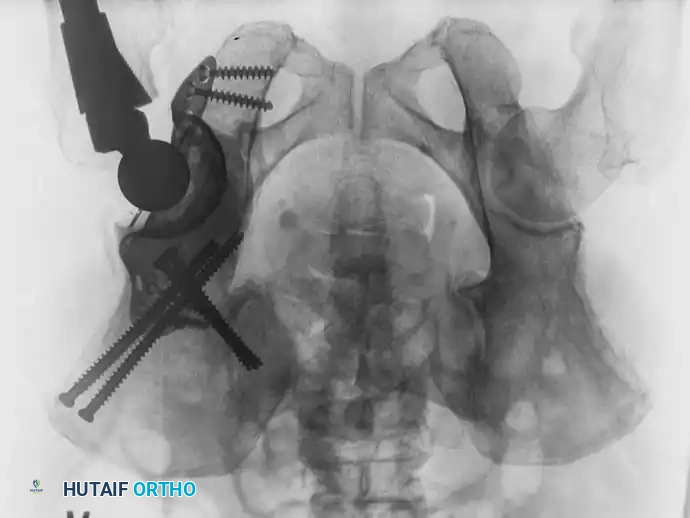

Fig. 22-23: (A, B) Radiograph and CT of a 66-year-old man with metastatic lung cancer destroying the right acetabular posterior column and wall. Preoperative embolization was performed to minimize blood loss. (C) Intraoperative view after curettage. Guidewires were placed from the defect to the posterior ilium and anterior iliac crest. Cannulated screws were placed over the wires to support the cement mantle. (D) An acetabular cage was placed, and the defect was filled with PMMA as the cup was cemented. (E) Postoperative radiograph demonstrating a stable construct.